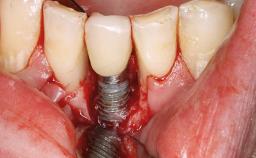

Management of a Technical Complication Caused by a Fractured Zirconia Abutment

A 24-year-old female patient was treated with an implant- supported crown for single-tooth replacement at site 11. A Straumann Bone Level RC implant (Institut Straumann AG, Basel, Switzerland) was placed with simultaneous bone augmentation, and the periimplant emergence profile was conditioned with a fixed implant-supported provisional crown. After finalization of the mucosal architecture, the clinical situation was transferred by means of a custom impression post for fabrication of an implant-supported screw-retained onepiece crown consisting of a CARES® zirconia abutment (Straumann) with a direct ceramic veneer.